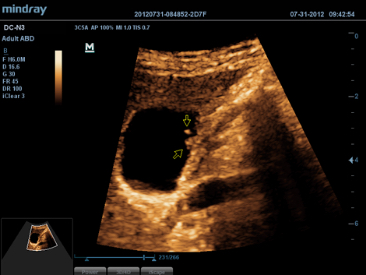

DC-N3 PRO

DC-N3 PRO? ??? ??? ??, ???, ???? ?? ???? ??? ?? ?????. ?? ??? DC-N3 PRO? ??? ??? ?? ??? ??? ???? ???? ??? ????? ??????. ???? ?? ???? ???? ?? ??? ???? ???? ???? ?? ? ????.

DC-N3 PRO? ??? ??? ?? ??? ??? ????? ?? ???? ???? ??? ?? ??? ??? ?? ???? ??? ?????. ?? ??? ??, ???, ??? ?? ??? ??? ??? ?????. ????? ???? ???? ????? ??? ???? ??? ?? ?? ?? ??? ??? ???? ??? ?????.